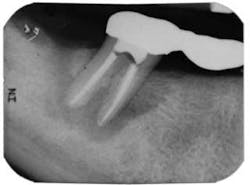

The patient was anesthetized using two carpules of 2% lidocaine for IANB and two carpules of Septocaine for long buccal infiltration. The tooth was isolated with a rubber dam and accessed under a dental operating microscope using long shank round burs and an Endo-Z bur for refining the access to cavity walls. Working length was determined using Root ZX II electronic apex locator. Instrumentation was completed using Xgates, and a combination between Protaper and Vortex Blue files with full-strength sodium hypochlorite irrigation. QMix was placed into the canals after irrigation and agitated with EndoActivator to remove the smear layer and for its antibacterial properties. Calcium hydroxide was placed, and the root canal was temporized with TERM temporary.

On the second appointment, the calcium hydroxide was rinsed out and the canals reinstrumented. QMix was again placed into the canals and agitated with EndoActivator. The canals were filled using warm vertical condensation with System B and Calamus backfill. The patient was given a six-month follow-up appointment and ibuprofen 600 mg for postoperative discomfort. I again stressed to the patient that the prognosis for this tooth was guarded. At the six-month follow-up appointment, the patient had been asymptomatic and there was clear evidence of healing.